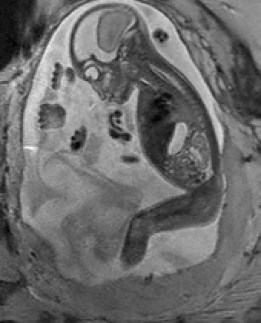

Reconstruction of Fetal Organs: Exemplary PVR and SVR reconstructions under motion introduced by kicking of the fetus are shown in Fig. 11. PVR reconstruction results show an improved visual appearance and less blurring in the region with severe motion artifacts (arrow). An example of a challenging clinical case with a kidney malformation in one of twin fetuses, is shown in Fig. 8. Our clinical partners confirmed that such complications are easier to examine and to quantify after PVR-based reconstruction.

Besides, multiple births is a case where classical SVR pipelines based on preprocessing steps to identify consistent rigid regions will likely fail. The presence of multiple instances of the same fetal structure is usually not considered in previous methods. Therefore, a fully automatic motion correction method for the whole uterus, as it is presented in this paper, is very desirable and will enable the application of standard 3D image analysis techniques, e.g., [20, 21].

In addition to reconstruction and motion correction of the whole uterus, we have also shown that our method works for multiple births cases with multiple fetuses sharing the same womb. These cases are more likely to have complications and to undergo MRI during pregnancy but would require extensive manual effort to be successfully reconstructed with state-of-the-art methods.